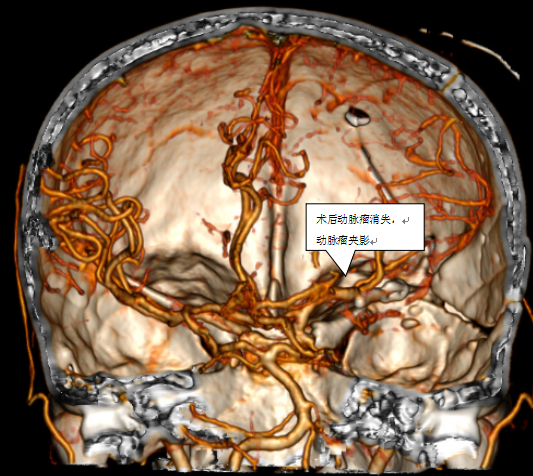

经过充分的术前讨论并上报手术计划后,血管组组长张珩手术团队开始了手术,张珩医生在余辉主治医师及王秋实主治医师的配合下,历经1小时成功夹闭动脉瘤并清除血肿,术后经过神经外科团队的精心治疗,顺利由神经外科重症监护室转入普通病房并康复出院。

凸出位置为动脉瘤